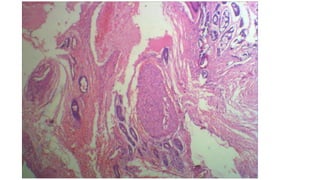

• Pleomorphic adenoma:

Most common tumor of salivary glands

Painless, slow growing tumor, composed of biphasic population of

epithelial and mesenchymal cells

Also called benign mixed tumor

Differentiating with ACC:

mesenchyme-like areas, no invasion, no perineurial invasion

• Pleomorphic adenoma: Mostcommon tumor of salivary glands Painless, slow growing tumor, composed of biphasic population of epithelial and mesenchymal cells Also called benign mixed tumor Differentiating with ACC: mesenchyme-like areas, no invasion, no perineurial invasion